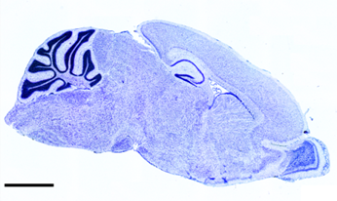

The brain is the regulatory ‘central station’ of all mammalian organisms. Important brain functions such as cell-to-cell communication, information processing, the formation and retrieval of memory as well as gene expression are regulated by distinct types of voltage-gated calcium channels and their auxiliary subunits. In order to mediate these functions calcium channels control the entry of calcium into neurons in a highly regulated manner. α2δ subunits have been traditionally envisioned as important factors for the localization, trafficking and stabilization of these channels in nerve cells. They also serve as drug targets for the anti-epileptic and anti-allodynic drugs gabapentin and pregabalin. In the ongoing project we developed novel techniques in order to study the specific roles of the individual subunits in single nerve cells as well as in the brain.

In cultured CNS neurons we study the specific functions of distinct L-type calcium channel splice variants to better understand their potential role in the etiology of Parkinson’s disease. These splice variants differ with respect to activation and inactivation properties and may thus differentially contribute to neuronal injury in Parkinson’s disease. Using established mRNA expression profiling we are characterizing the exact isoform composition of such channel complexes in relevant neurons. To study their specific functions we generated tagged channels to analyze the differential targeting properties of these splice variants in hippocampal neurons and the roles of their interaction with known scaffold proteins for dendritic stability and remodeling. Because our recent findings indicated that the calcium channel β4 subunit is targeted into the nucleus of quiescent neurons, we are investigating the role of β4 in gene regulation. We recently identified, that nuclear β4 proteins can regulate the expression of genes involved in neuronal activity and communication, thereby providing a novel feedback mechanism between synaptic calcium channels and the nucleus.